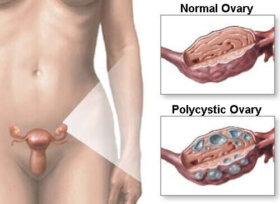

난소에 문제가 생기면 생리가 불규칙해지고 체중 감량이 어려워진다. 가임기 여성에게 잘 발생하는 다낭성 난소 증후군에 걸리면 여드름이 나면서 탈모와 함께…